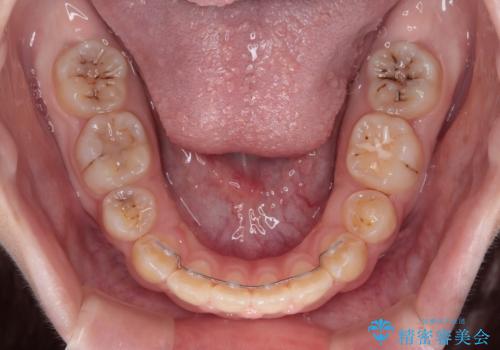

当初は舌のトレーニングがうまくできていなかったのですが、途中から奏効し、非常に短い期間で治療を終えることができました。

- 矯正治療後の保定が不十分だと後戻り(元の位置に戻ろうとする動き)をします